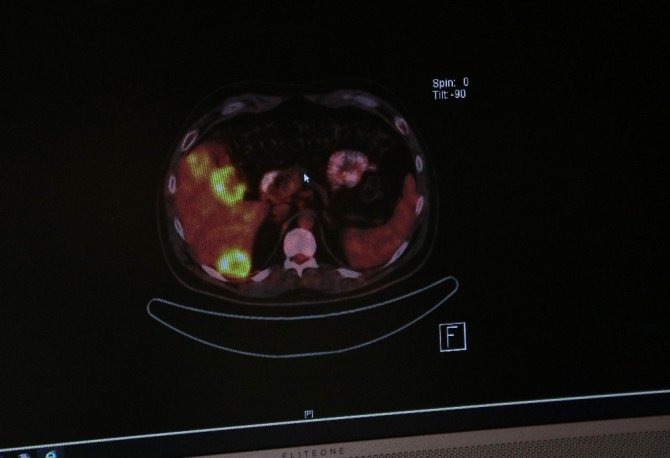

Korona virüse yakalanabileceği endişesi ile hastaneye gitmeyi erteleyen pek çok kişi, kanserde erken tanı şansını kaybediyor. Tıbbi Onkoloji Uzmanı Prof. Dr. Züleyha Çalıkuşu, dünyada her yıl 18 milyon kişinin ilk kez kanser tanısı aldığını belirterek, "Bu yıl kanser hastalığına yakalananların tanıları daha geç evrelerde konmuş ve tedavilerine daha geç başlanmış olacağı için ortalama tedavi başarıları da geçen senelere göre daha düşük olacak. İnsanlar hastanelere gitmekten korkmamalılar" dedi.

Konuyla ilgili Acıbadem Adana Hastanesi Tıbbi Onkoloji Uzmanı Prof. Dr. Züleyha Çalıkuşu, İHA'ya açıklamalarda bulundu. Kanser hastalarında erken teşhisin önemli olduğunu vurgulayan Çalıkuşu, "Şu anda doğal olarak herkesin tek gündemi, korona virüs. Kanser gibi diğer riskli hastalıklar, adeta kamuoyunun gündeminden düşmüş durumda. Bu da, erken teşhis oranında ciddi bir düşme anlamına geliyor. Biliyoruz ki, tüm dünyada her yıl 18 milyon kişi, ülkemizde de 160 binden fazla kişi ilk kez kanser tanısı alıyor. Eğer bu kişiler tarama testlerini yaptırmaz, belirtileri göz ardı ederlerse, kanser ilerlemiş olacak. Dolayısıyla bu yıl kanser hastalığına yakalananların tanıları daha geç evrelerde konmuş ve tedavilerine daha geç başlanmış olacağı için ortalama tedavi başarıları da geçen senelere göre daha düşük olacak. Bu nedenle sağlık kontrollerimizi ihmal etmememiz gerekiyor. Hijyen kurallarına dikkat ederek, sosyal mesafeye uyarak, maske takarak hastanelere gitmekten çekinmemeliyiz" diye konuştu.

Pandemi döneminde pek çok hastanın geç evrede tanısının konulduğunu anlatan Züheyla Çalıkuşu, "Bize gelen pek çok hastada da aynı sorunları yaşadık. Daha erken tanısı konulabileceği halde pandemi nedeniyle korkarak 5-6 aydır hastaneye gitmeyen ve ileri evrede gelen hastalarımız oldu. Oysa bu hastalar, daha erken gelseydi hem tedavi şansları daha yüksek olacaktı hem de hayat kaliteleri artacaktı. Özellikle vurgulamak isterim, hastalar hastane gitmekten çekinmemeliler. Hastanelerde maske, mesafe ve hijyen kurallarına dikkat ediliyor. Her hastadan sonra kullanılan aletler sterilize ediliyor. Hastalar kendi hijyen kurallarına dikkat ederek hastaneye gelmeliler" ifadelerini kullandı.